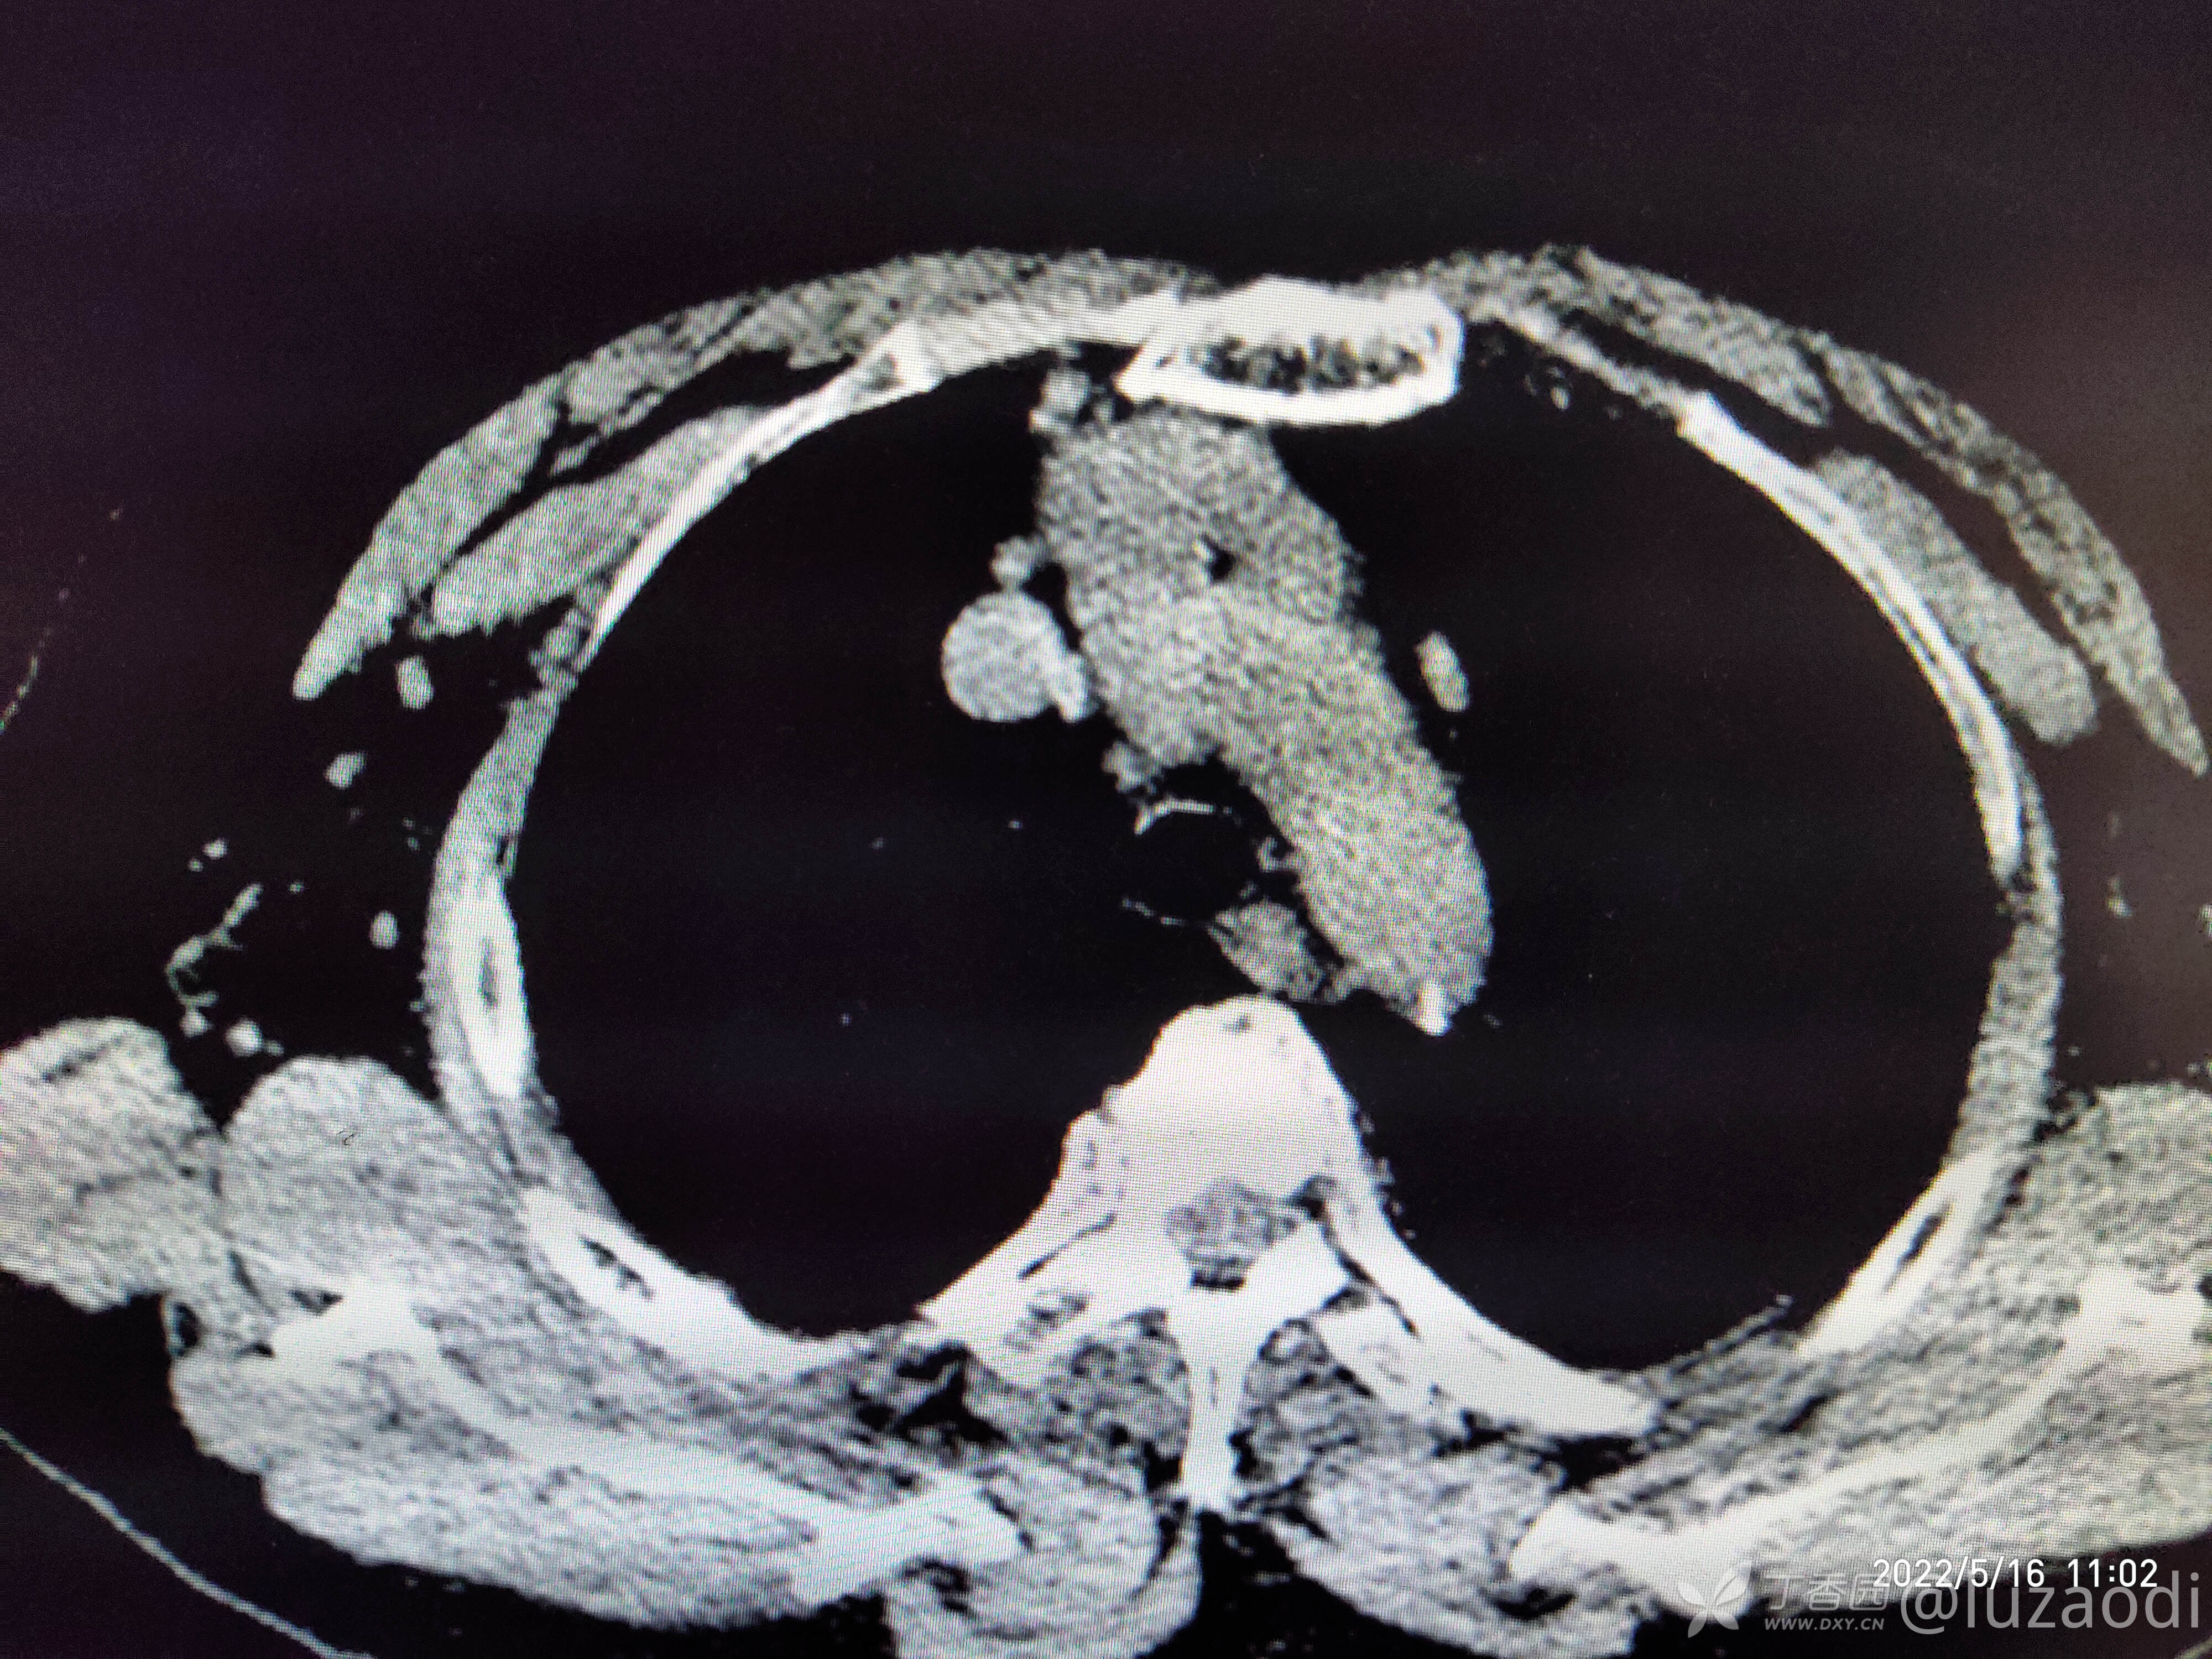

治疗经过:入院后患者仅有乏力,未见明显神经定位征。近期无发热、咳嗽、腹泻症状。遂予血糖、心电图、生化检查及影像检查,结果如下:

我去。。。。。视频只能上传一个,头颅CT上传不了,我直接说报告吧。头颅CT报腔隙性脑梗。

到目前为止,所有的资料如上面所描述。那么请大家讨论一下这个病人可能是何种疾病,下一步应该怎么做?如何告知患者病情以及可能的风险?欢迎各位新手和老鸟留言讨论,看看大家的思维及诊疗,或者是指出到目前为止还有什么需要做的诊疗措施?错也不要紧,没有错哪有对?在我这错好过在病人身上错。要学技术就不能要脸,各位